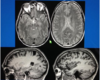

En 25-årig kvinde klager over snurrende fornemmelser i benene og på abdomen op til ribbenskurvaturen. Det har stået på 1 uge og der er ledsagende urge inkontinens og tunghed i benene.

Hvad viser MR-scanningen ?

a. MR scanningen er normal.

b. Der er en vaskulær læsion i medulla (T2 vægtet)

c. Der er forandring tydende på myelitis

d. Der ses artefakt i medulla

En 25-årig kvinde klager over snurrende fornemmelser i benene og på abdomen op til ribbenskurvaturen. Det har stået på 1 uge og der er ledsagende urge inkontinens og tunghed i benene.

Hvad viser MR-scanningen ?

a. MR scanningen er normal.

b. Der er en vaskulær læsion i medulla (T2 vægtet)

c. Der er forandring tydende på myelitis

d. Der ses artefakt i medulla